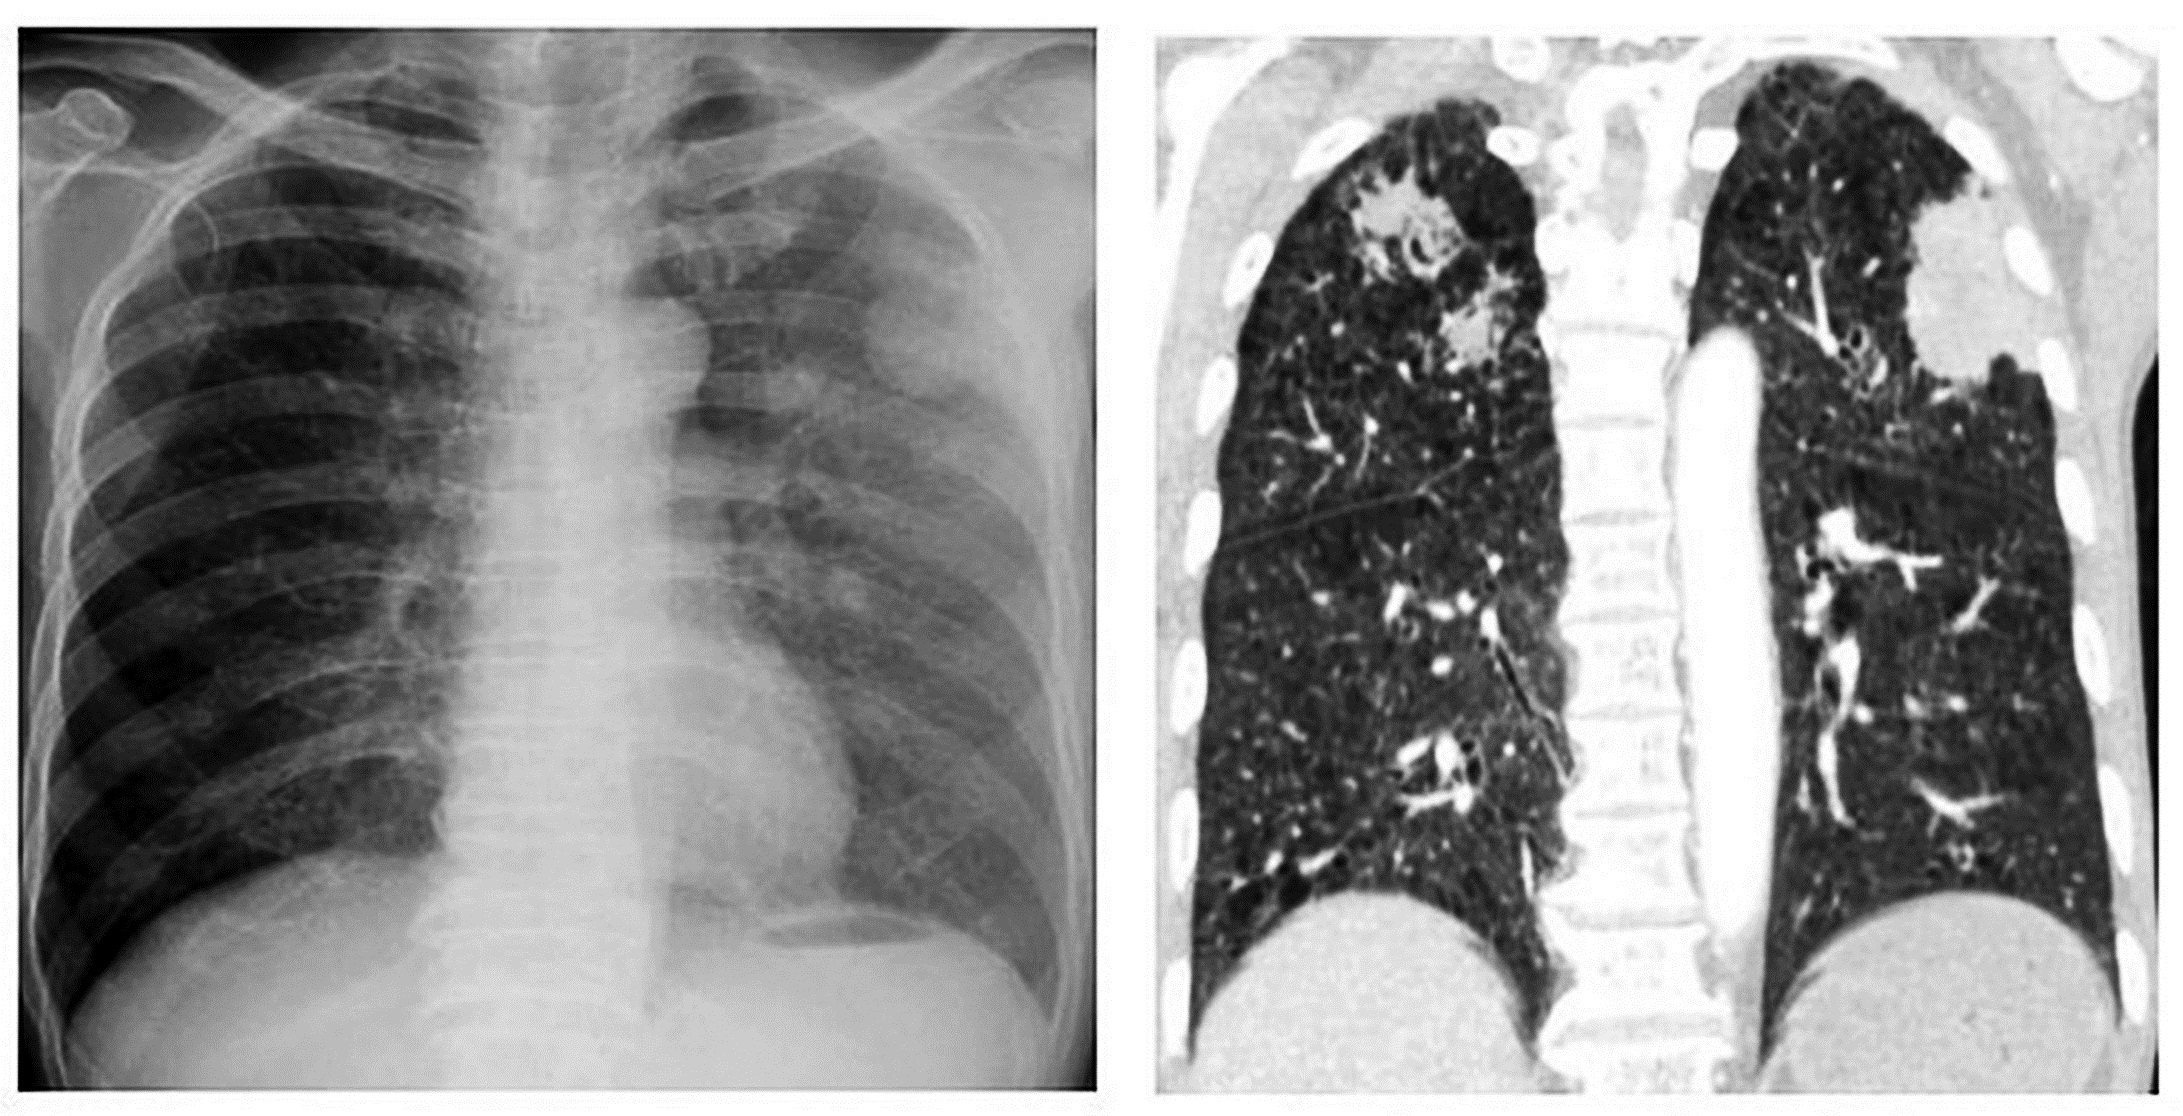

Tại khoa hô hấp – hồi sức tim mạch, kết quả chụp cắt lớp vi tính ngực và ổ bụng cho thấy hẹp môn vị nghi do ký sinh trùng, tổn thương phổi hoại tử hai bên. Xét nghiệm dịch rửa phế quản phát hiện ký sinh trùng, bệnh nhân được chẩn đoán nhiễm giun lươn nặng ở phổi và điều trị đặc hiệu theo phác đồ.

Tổn thương phổi hoại tử hai bên của người bệnh – Ảnh: BVCC